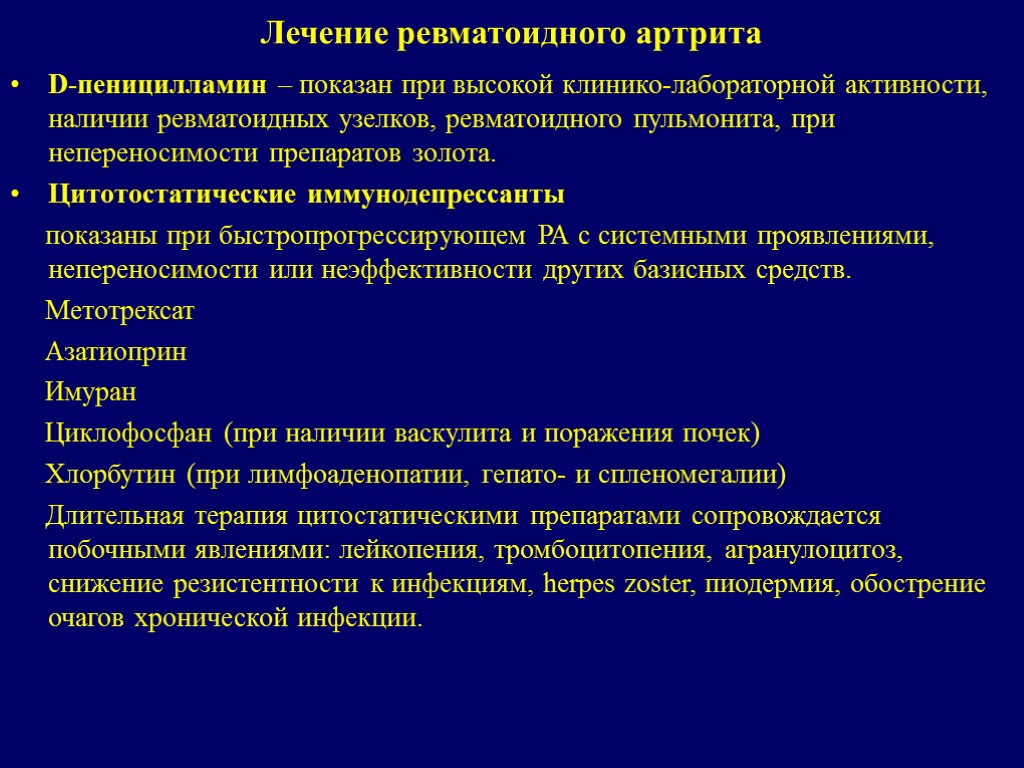

Базисные препараты для лечения артрита применяют сразу после установления диагноза. Базисная терапия ревматоидного артрита включает в себя такие лекарственные препараты: D-пеницилламин, метотрексат, сульфасалазин, циклофосфан, аминохинолиновые препараты, циклоспорин А (сандиммун), азатиоприн, энбрел (этанерцепт), ремикейд (инфликсимаб), вобэнзим, флогэнзим, лефлуномид.

Базисная терапия ревматоидного артрита включает в себя такие лекарственные препараты: D-пеницилламин, метотрексат, сульфасалазин, циклофосфан, аминохинолиновые препараты, циклоспорин А (сандиммун), азатиоприн, энбрел (этанерцепт), ремикейд (инфликсимаб), вобэнзим, флогэнзим, лефлуномид.

Малоэффективные препараты из данного списка после 2-3 месяцев приема должны быть заменены, или использоваться в комбинации с малыми дозами гормонов (третья группа лекарств). По истечению шести месяцев должен быть разработан курс действенной базисной терапии. Для этого необходимо тщательно отслеживать возможные побочные эффекты препаратов и изменения в течении болезни.